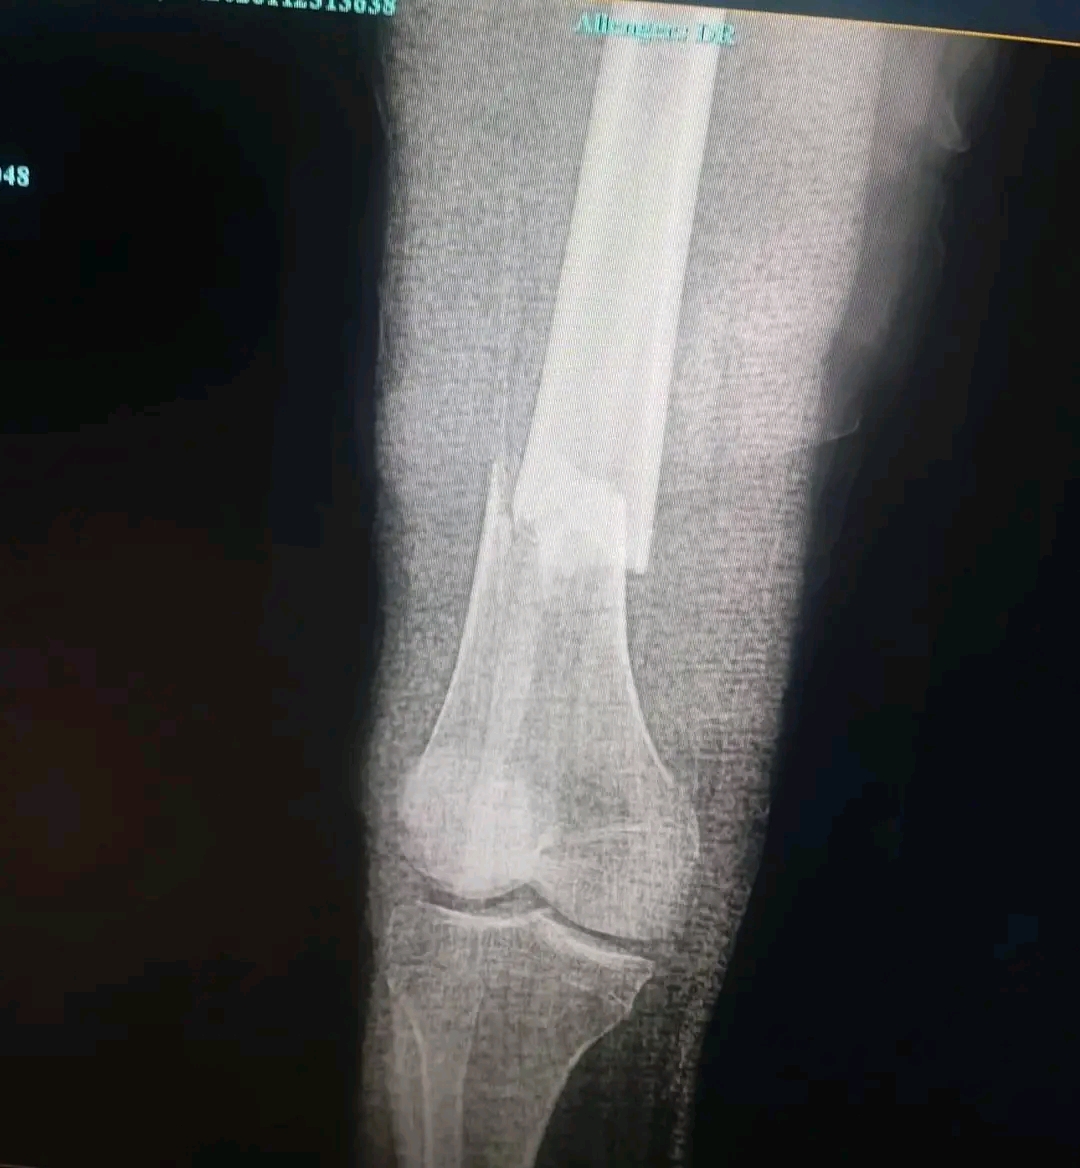

O incidente deu-se quando um poste de energia elétrica caiu sobre o técnico em pleno horário de expediente. Os exames de raio-X realizados na unidade hospitalar confirmaram a gravidade do impacto, que resultou na fratura do osso da sua perna direita.